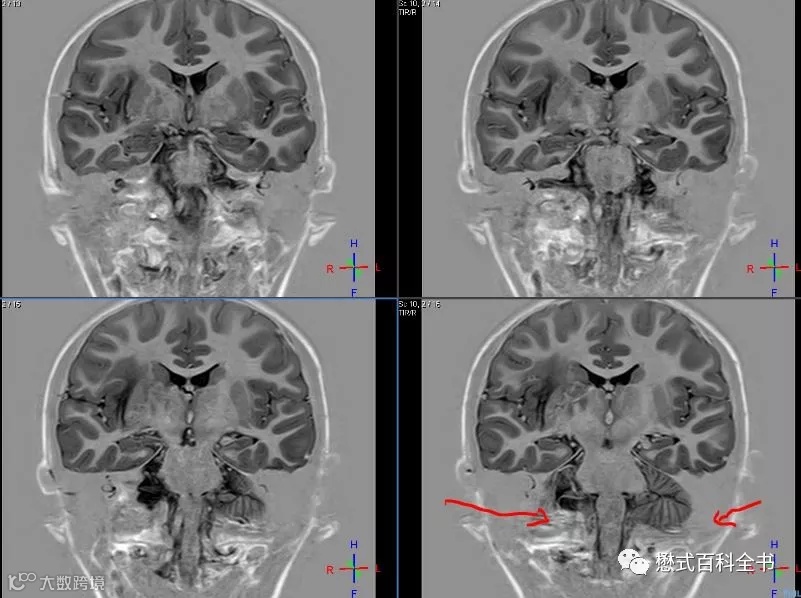

图15:IR序列实图

如图15,IR序列采用实图重建,背景是灰色的。虽然不会产生反弹点伪影,但是注意看颈部,还是有些相位错误导致的小伪影。